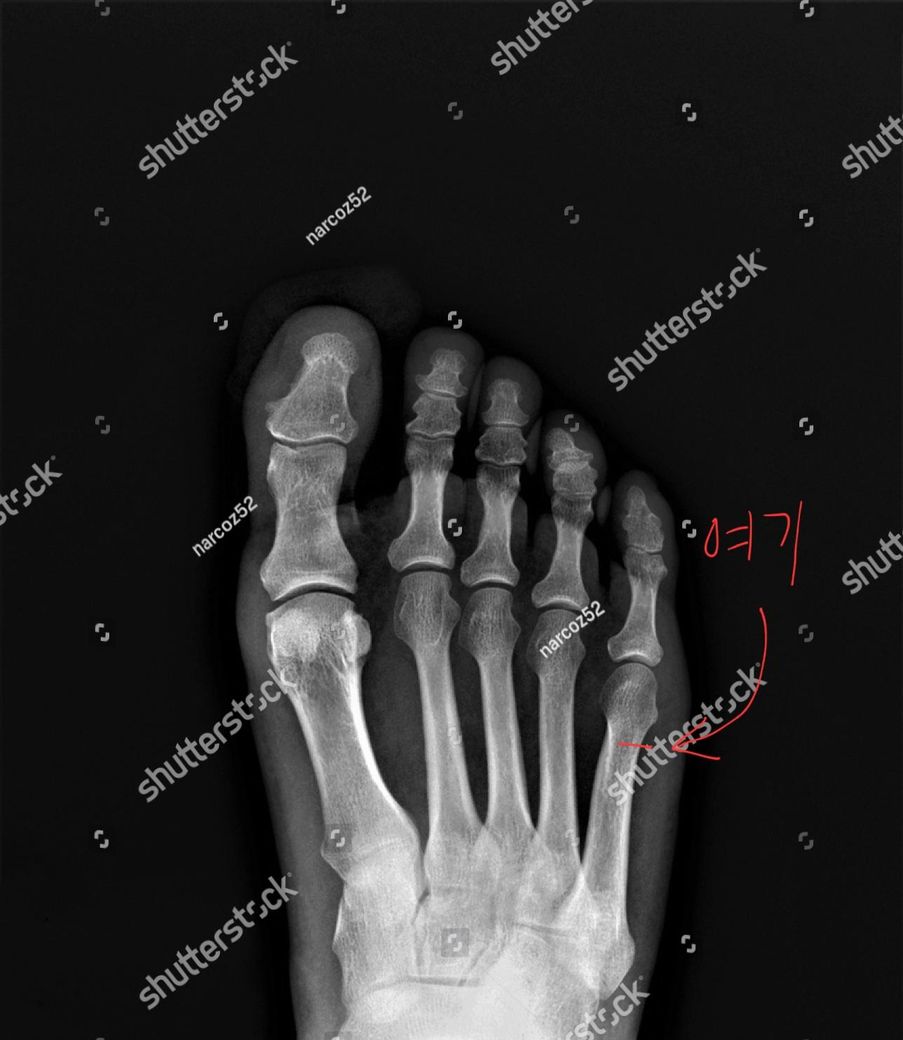

발을 접질러서 뼈에 금이 갔는데 어느정도 걸을수 있을때 까지 나을려면 얼마나 걸리나요?

제목 그대로 발을 접질러 새끼발가락을 연결하는 뼈 중간쯤에 실금이 갔는데 어느정도 지나야 적당히 반깁스를 풀고 걸을수있나요?.

새끼발가락 골절로 불편이 있으시군요.

골절 부위가 유합이 되기 위해서는 4주-8주 정도 회복기간이 필요할 것입니다.